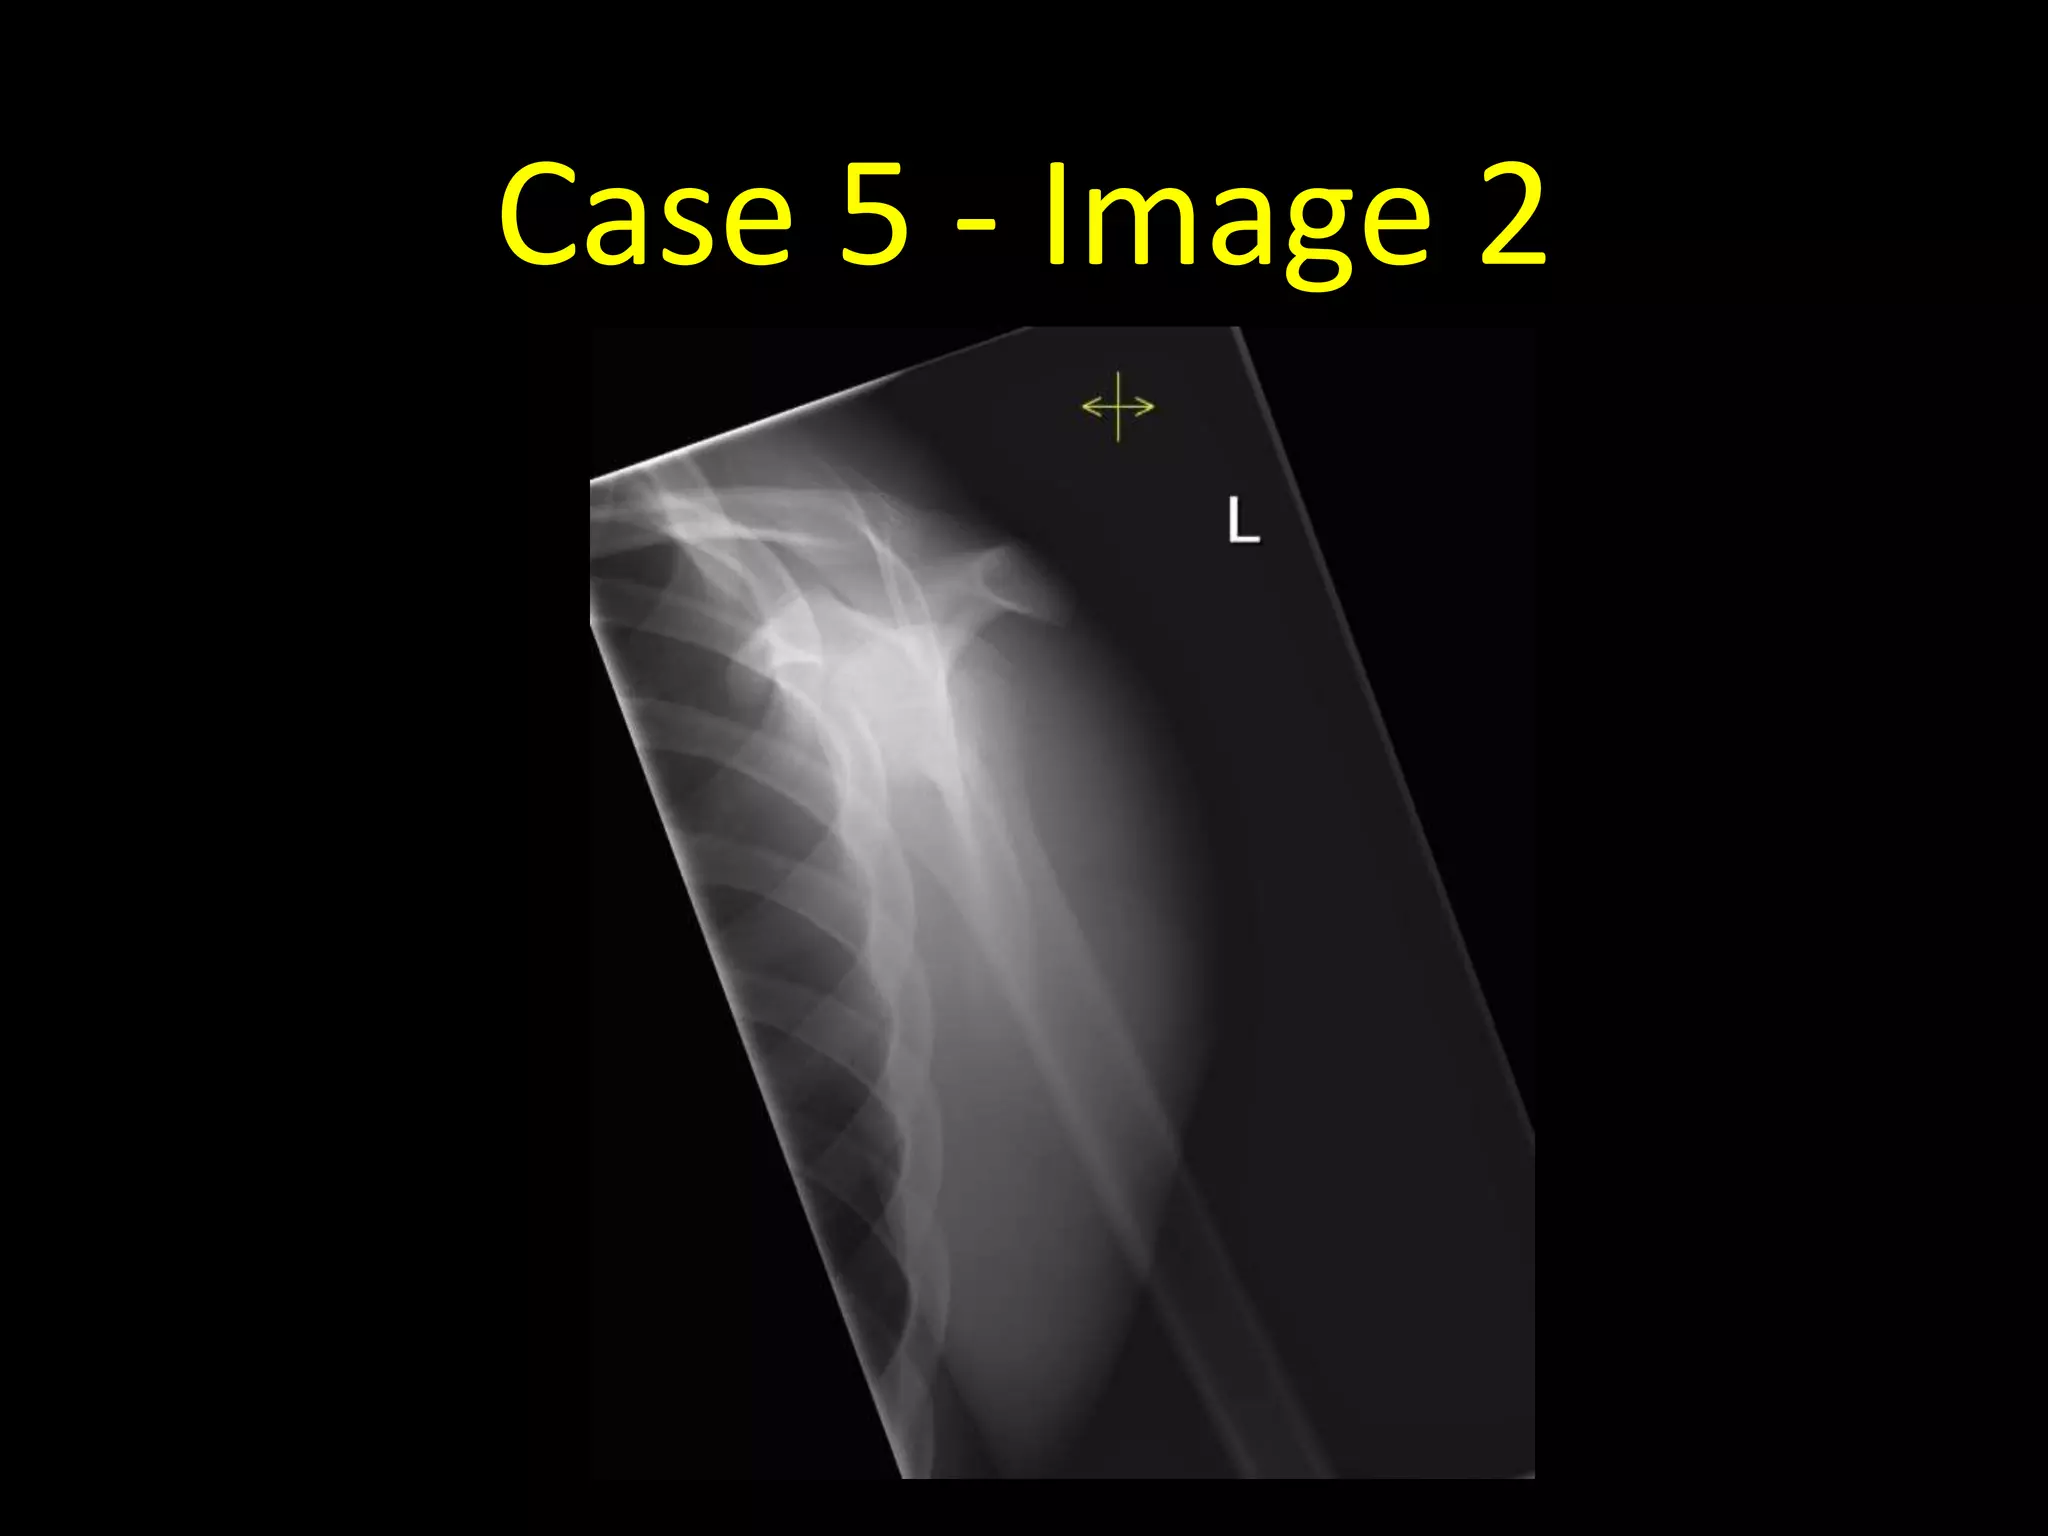

Case 5

• 15 year old with pain in the left shoulder after a fall

Case 5 - Image 1

Case 5 - Image 2

• Normal radiographs!

• Don’t be fooled by the left proximal

humeral growth plate (arrows)

• There appear to be two lines through

the left proximal humerus as the growth

plate runs obliquely through the plane

of the radiograph

• Note there are also growth plates visible

at the acromion and coracoid processes

• Remember in young patients to consider

if what you’re looking at might be a

growth plate